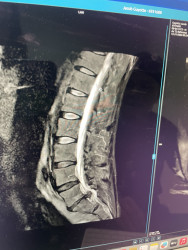

My two boys. I want them to believe in them selves. Also having a spine injury , 2 surgeries . You have ti work harder.